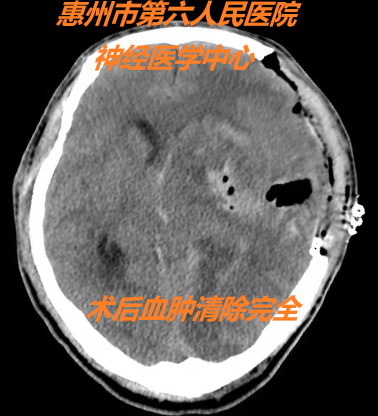

病情就是命令。一旦發(fā)生腦疝,就意味著時間就是生命,晚幾分鐘都有可能導(dǎo)致嚴(yán)重殘疾或長期植物狀態(tài)甚至死亡。神經(jīng)外科醫(yī)療團隊立即與手術(shù)室、麻醉科取得聯(lián)系,開通急診手術(shù)綠色通道,直接將病人送入手術(shù)室,給患者創(chuàng)造一個最佳的“黃金搶救時段”,用最短的時間做好術(shù)前準(zhǔn)備。神經(jīng)外科主任余永強、麻醉科主任蔡劍波帶領(lǐng)神經(jīng)外科及手術(shù)室團隊立即進行插管全麻開顱顯微手術(shù)搶救,清除腦內(nèi)血腫。術(shù)后CT顯示血腫全部清除,患者生命體征平穩(wěn),轉(zhuǎn)入神經(jīng)外科重癥監(jiān)護室繼續(xù)治療。

患者生命垂危,搶救刻不容緩!神經(jīng)外科主任醫(yī)師余永強、副主任醫(yī)師劉立國立即帶領(lǐng)介入團隊為患者進行左側(cè)小腦前動脈動脈瘤栓塞+左側(cè)小腦前動脈動靜脈畸形栓塞術(shù)。介入手術(shù)難度大、風(fēng)險高,主刀醫(yī)生需要打起十二分的精神,“穩(wěn)如泰山”“一針到位”。經(jīng)過介入團隊和介入室全體醫(yī)護的認(rèn)真努力,手術(shù)取得成功,患者左側(cè)小腦前動脈瘤及畸形的動靜脈完全栓塞,患者轉(zhuǎn)入神經(jīng)外科重癥監(jiān)護室繼續(xù)治療。